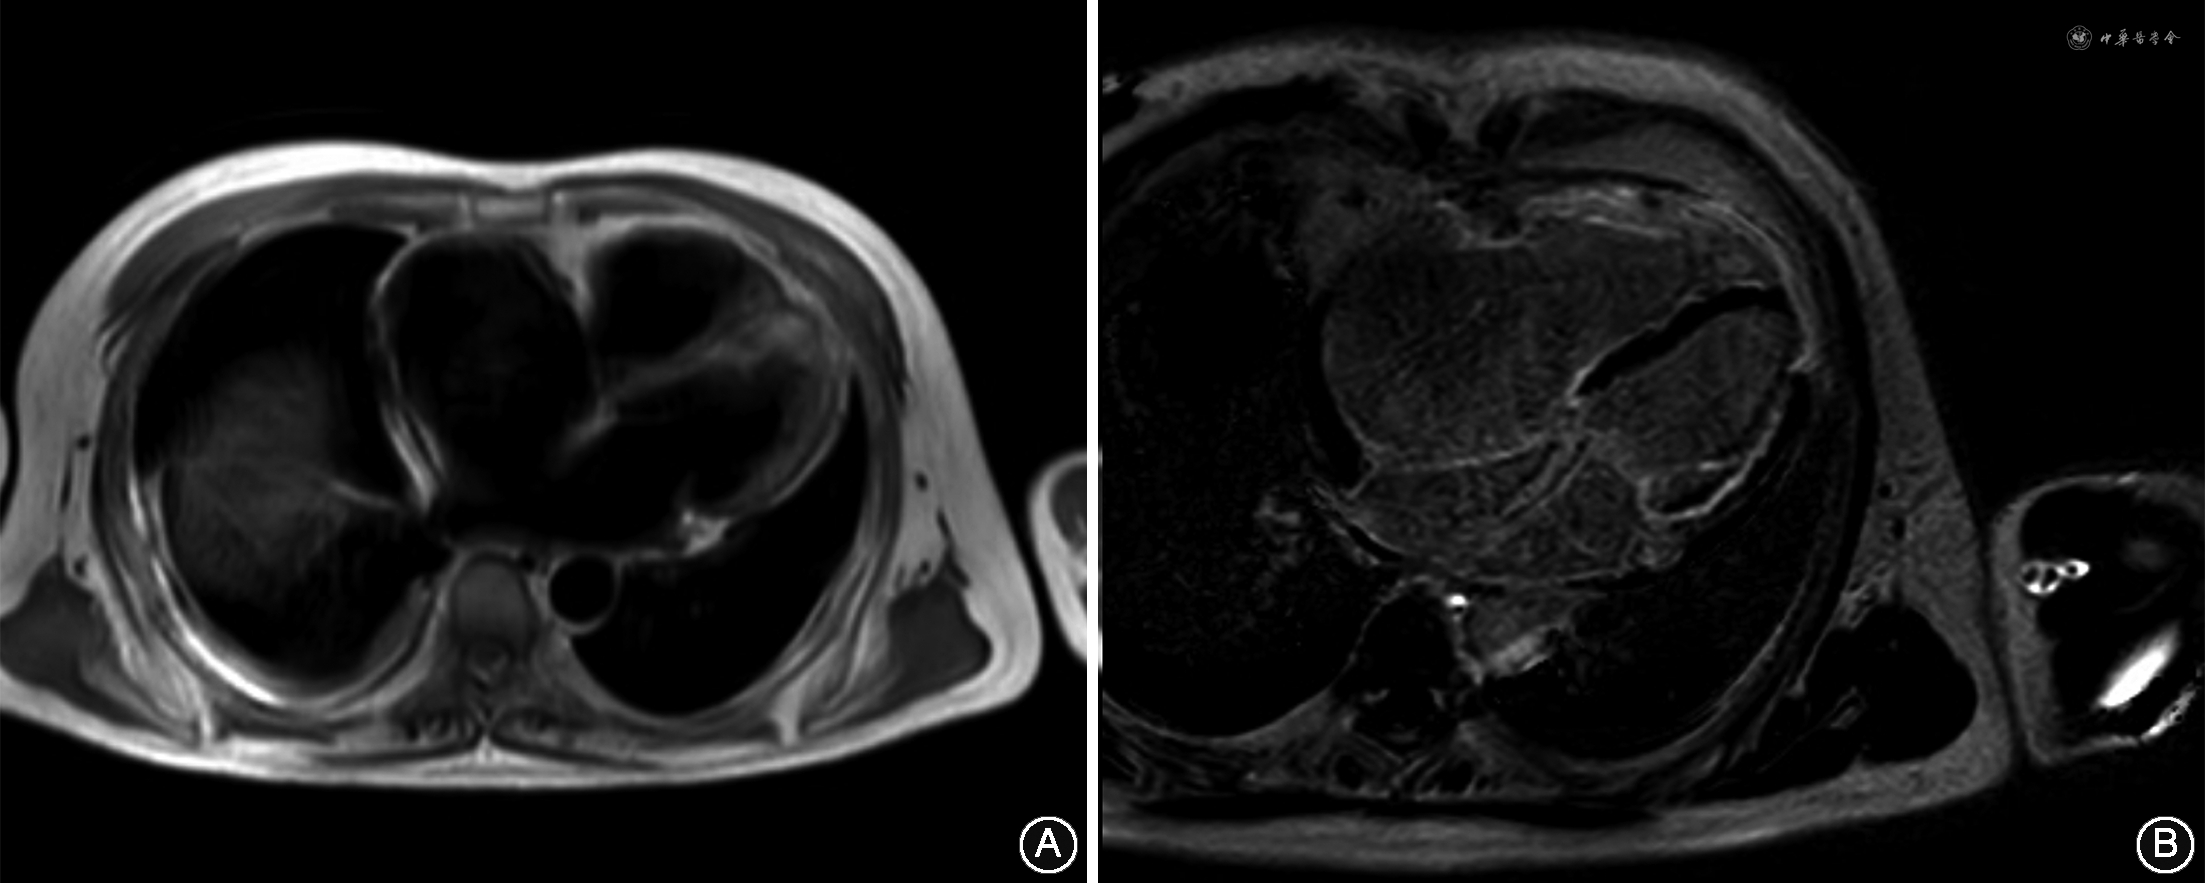

患者男性,48岁,因“间断呼吸困难8年,双下肢水肿2年,加重3月”于2020年6月11日就诊于吉林大学第一医院。既往因双下肢无力伴小腿肌肉萎缩30年,行肌电图检查提示肌源性损害,肌肉活检病理为肌营养不良改变。基因测序结果提示结蛋白(Desmin,DES)基因第8外显子区域纯合错义突变(c.1366G>A),编码氨基酸p.G456R(甘氨酸>精氨酸)。先证者父母为非近亲婚配,均为该位点杂合变异携带者,无肌无力等临床表现。辅助检查:血清肌酸激酶(creatine kinase,CK)223 U/L。N末端B型利钠肽前体(N terminal-pro B type natriuretic peptide,NT-proBNP)1 770 pg/mL。心肌肌钙蛋白I(cardiac troponin I,cTnI)正常范围。血气分析示:氧分压89 mmHg(1 mmHg = 0.133 kPa),二氧化碳分压34 mmHg。心电图示:窦性心律,不完全性右束支传导阻滞,左前分支传导阻滞,房性期前收缩和室性期前收缩(图1)。核素肺通气-灌注显像未见异常。肺功能检查示:用力肺活量占预计值的48%,提示限制性通气功能障碍。超声心动图示:左心室射血分数(left ventricular ejection fraction,LVEF)46%(M型Teichholz法),右心室内径26 mm,右心房径54 mm×64 mm,右心室壁搏动弥漫性减弱,三尖瓣环收缩期位移(tricuspid annular plane systolic excursion,TAPSE)12 mm,三尖瓣重度返流。心脏磁共振成像(magnetic resonance imaging,MRI)(图2)示:左心房、左心室内径正常,右心房前后61 mm,右心室横径43m,延扫扫描示:左心室侧壁、心尖部、右心室壁弥漫条形强化,部分呈透壁样强化,LVEF 35%,心输出量2.61 L/min。临床诊断:结蛋白肌病心肌损害、右心扩张、全心衰竭、心功能3级(NYHA分级)、心律失常、右束支传导阻滞、左前分支传导阻滞、房性期前收缩、室性期前收缩。给予利尿(呋塞米、螺内酯口服)、强心(地高辛口服)治疗,沙库巴曲/缬沙坦50 mg 2次/d口服,患者呼吸困难缓解,夜间阵发性呼吸困难和双下肢水肿消失。2个月后复查NT-proBNP 1 090 pg/mL。而后患者因“心悸1天”于2020年12月18日再次就诊于我院。体格检查:脉搏98次/min,呼吸19次/min,血压112/70 mmHg。颈静脉无怒张,双肺呼吸音粗,未闻及啰音。心率98次/min,律不齐,剑突下可闻及2/6级收缩期吹风样杂音。双侧腓肠肌萎缩。肌力检查:双下肢远端Ⅳ级,双足背伸Ⅱ级。辅助检查:B型钠尿肽(B type natriuretic peptide,BNP)934 pg/mL。地高辛浓度:0.43 ng/mL。血清离子及cTnI水平正常范围。动脉血气分析(鼻导管吸氧,氧流量3L/min)示氧分压103 mmHg,二氧化碳分压37 mmHg。患者心悸发作时未做心电图,入院后心电图示:异位心律,阵发性心房扑动(2∶1传导),非特异性室内传导阻滞、QT间期延长(图3)。超声心动图示:LVEF 29%(M型Teichholz法),右心室前后径34 mm,右心房径55 mm×68 mm,TAPSE 8 mm,右心功能减低,三尖瓣中度返流。心房扑动诊断明确,入院第5天患者行心脏射频消融术+临时起搏器植入术:术前食管超声心动图及左心房CT未见左心房及左心耳血栓,术中应用星形标测电极,标测结果为三尖瓣峡部逆钟样折返心房扑动,沿三尖瓣峡部行线性射频消融(图4),心房扑动终止恢复窦性心律,间断出现交界性心律,给予心脏临时起搏,术后HV间期69 ms。患者术后心电图示窦性心律,非特异性室内传导阻滞,QT间期延长。术后第2天拔除临时起搏器,出院后给予利尿(呋塞米口服)、抗凝(利伐沙班口服)、辅酶Q10治疗,因血压较低,沙库巴曲/缬沙坦减量为25 mg,2次/d口服,嘱患者定期随访复查。

超声心动图、心脏MRI可明确心肌病变范围和程度以及定量评估心脏功能。结蛋白肌病相关的心肌病目前以扩张型心肌病或限制型心肌病最常见。本例患者入院多以体循环淤血为主要临床表现,超声心动图提示右心损害为重,符合限制型心肌病相关表现,但心脏MRI提示左心室心肌亦受累,LVEF值明显减低,故本例患者为双侧心室心肌受累,这在结蛋白肌病导致的心肌损害中较为少见。本病例患者右心房扩张,导致右心房重构,有利于形成折返环路,致使心房搏动过快,最终导致心房扑动的发生。相反,由于心房扑动时心房失去辅助泵功能以及心房、心室运动失同步性,可进一步诱发和加重心力衰竭,两者形成恶性循环,可明显降低活动耐量。此外,结蛋白还表达于蒲肯野纤维及闰盘,因此,结蛋白肌病常引起传导阻滞型心律失常[5]。本病例患者心电图表现为非特异性室内传导阻滞,提示了心脏传导系统受累。如病变加重,则可发生分支水平的完全性房室传导阻滞,导致患者出现晕厥或心原性猝死。